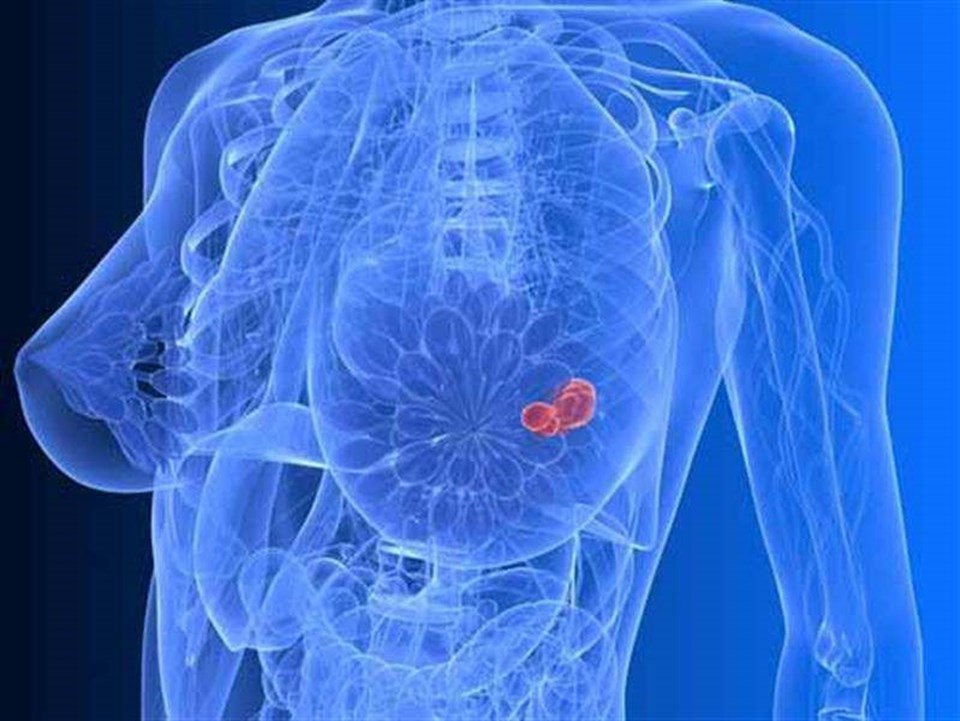

Dünyada her 8 kadından birinde görülen ve kadınlarda en çok ölüme yol açan meme kanseri de bu gelişmelerden nasibini alan hastalıklar arasında. Teknoloji ürünü yöntemlerle kanser hücresinin genetik haritası çıkartılıyor ve o genetik yapıya etki eden akıllı ilaçlarla tümör yok ediliyor.

Demir’e göre yöntem meme kanseriyle mücadele açısından çok önemli, çünkü: “Tümörün genetik haritası çıkartılıyor, böylece bazen sadece böbrek tümörlerinde var olduğunu düşündüğümüz bir mutasyonun, meme tümörlerinde de olduğunu görüp bu mutasyona özgü akıllı ilacı kullanabiliyoruz.”